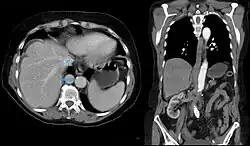

Azygoskontinuität bei einem Patienten mit Situs inversus. Darstellung der nicht kontrastierten deutlich erweiterten V. azygos neben der kontrastierten Aorta in einer CT-Untersuchung der Koronarien.